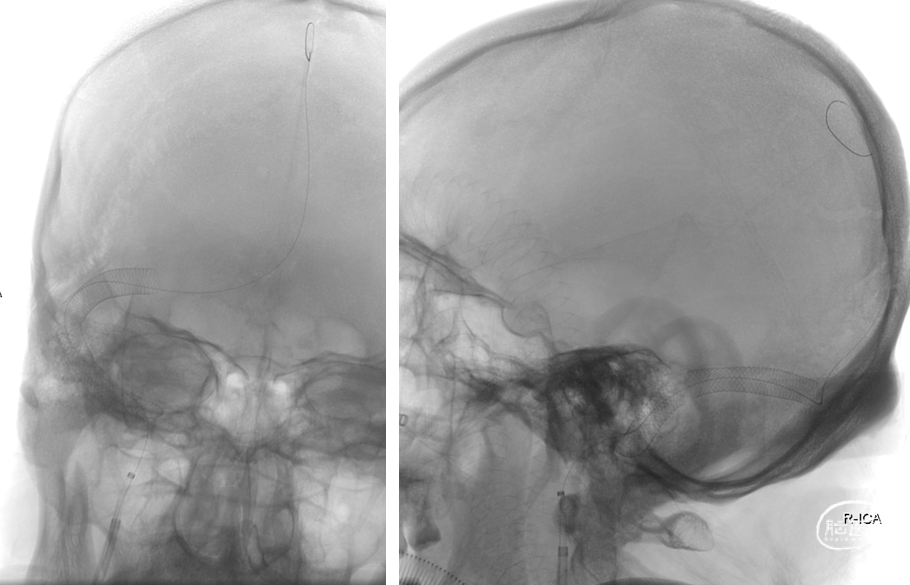

颅内正侧位造影:上矢状窦显影明显改善,右侧横窦及乙状窦显影良好,静脉回流良好

术后复查头颅CT(2022-1-15)